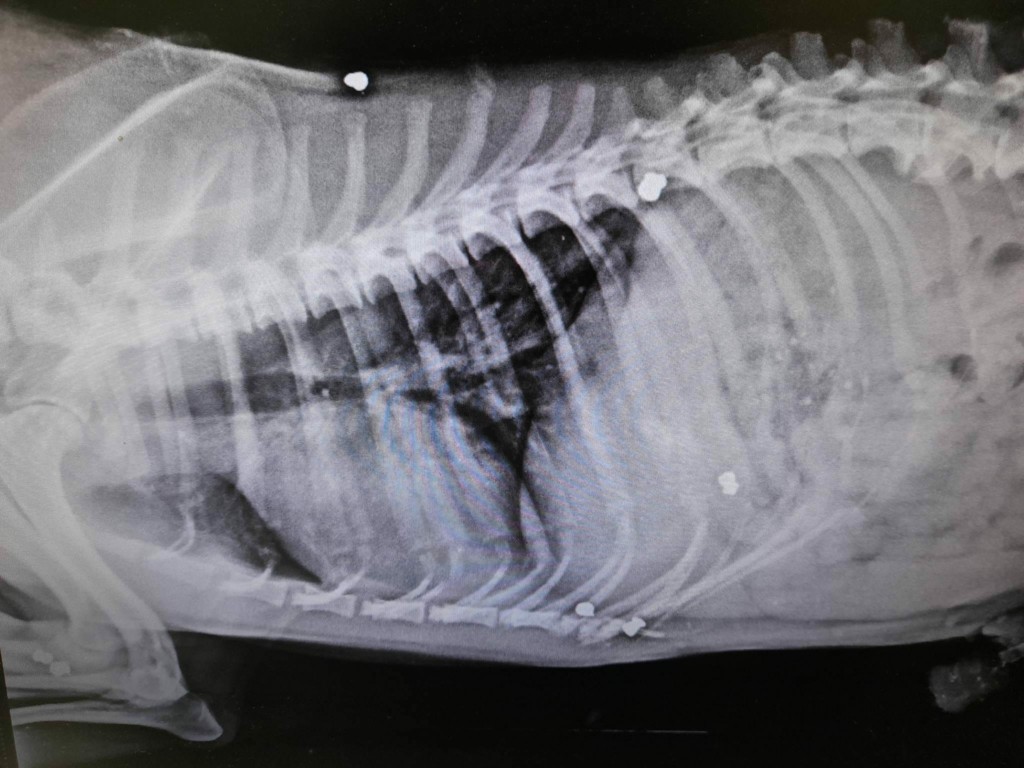

Το αδέσποτο σκυλάκι φαίνεται να έχει πυροβοληθεί τουλάχιστον δέκα φορές με αεροβόλο όπλο.

Το νέο περιστατικό κακοποίησης ζώων φέρνει στο φως ο Φιλοζωικός Σύλλογος Εμμανουήλ Παππά, αναφέροντας ότι ο Smiley, όπως ήταν το όνομά του, δέχθηκε τουλάχιστον 10 πυροβολισμούς από αεροβόλο όπλο που κρατούσε στα χέρια του ασυνείδητος κάτοικος του χωριού, με αποτέλεσμα να βρει φρικτό θάνατο.